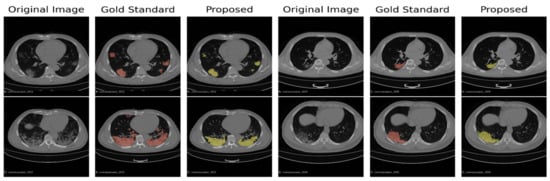

We show in Figure 2 the distribution of the individual scores (Sensitivity, Specificity, Precision, and F1 score). The scores were obtained by the average of the whole 15 scans (overall) on the 10 corona cases (CORONACASES OVERALL) and on the five gold standard (GOLD STD OVERALL). In Figure 3 and Figure 4, we show a visual comparison between the achieved segmentation and the ground truth labels (both for corona cases and the gold standard).

The examples reported in Figure 3 and Figure 4 show how the non-supervised segmentation method proposed in this paper is able to approximate the gold standard results with satisfactory results.

Figure 3. A comparison between the ground truth and the results obtained by the proposed pipeline for the corona cases segmentation. In green are highlighted the GGO areas identified by the experts, and in red, those identified by our segmentation pipeline, respectively.

Figure 4. A comparison between the proposed automated segmentation pipeline and a gold standard segmentation manually performed by an expert radiologist.